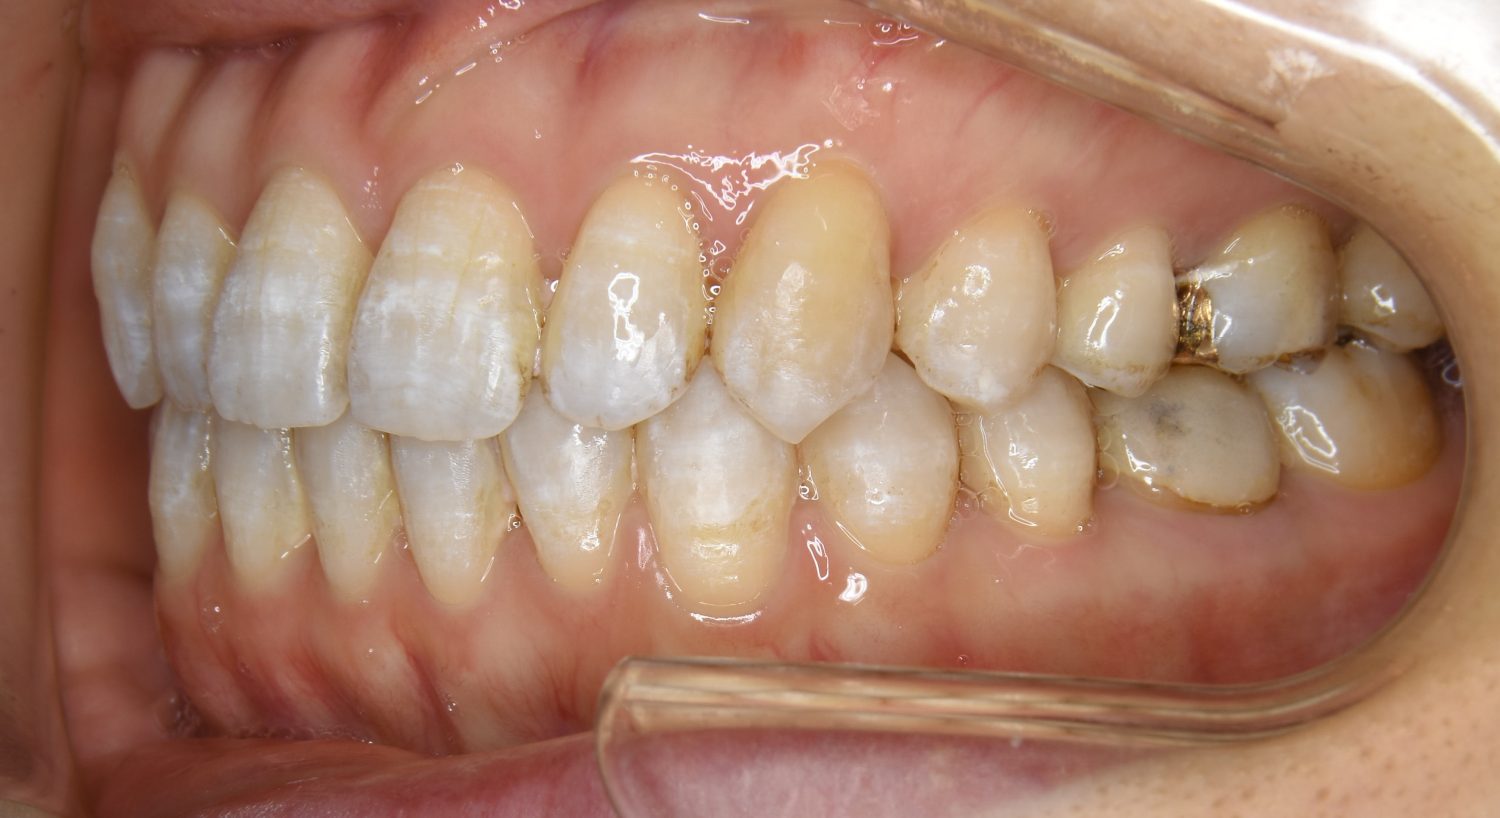

前歯部開咬の症例紹介②

Before

主訴

前歯で物が噛めない

治療内容

上下ラビアルブラケット(唇側装置)に矯正用アンカースクリューを併用し非抜歯で治療を行いました。

治療費

1,000,000 円(税込)

治療期間

26ヶ月

通院回数

27回

想定されたリスク

※歯根吸収、歯肉退縮、歯髄壊死、顎関節症状

上下の前歯が開いており前歯では全く噛めていない状態でした。臼歯の圧下を行うことで機能面のみでなく審美面も改善しました。